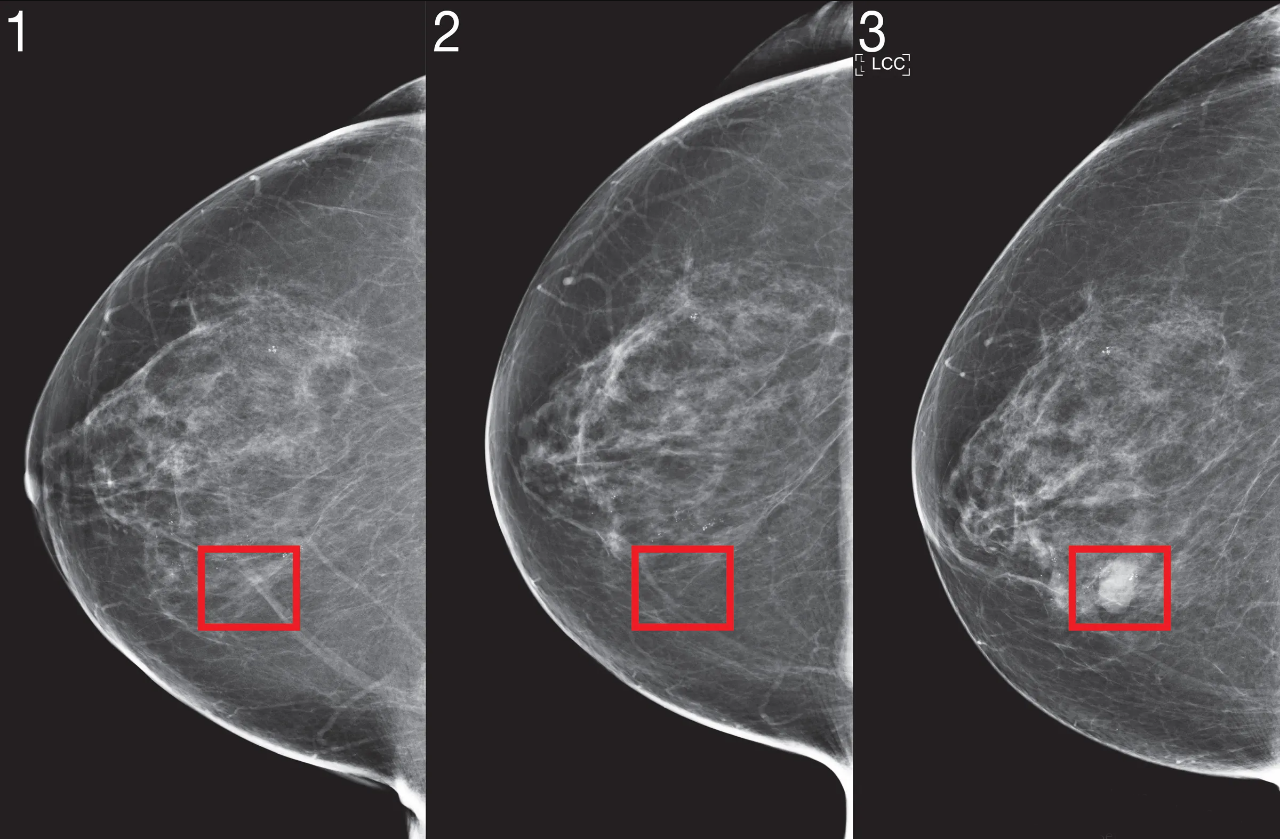

Cách phát hiện ung thư vú: Những phương pháp quan trọng giúp phát hiện

Ung thư vú là một trong những loại ung thư phổ biến nhất ở phụ nữ. Tuy nhiên, nếu phát hiện sớm, tỷ lệ điều trị thành công rất cao. Việc phát...

Quy trình khám ung thư vú: Các bước tầm soát và chẩn đoán hiệu quả

Ung thư vú là một trong những bệnh ung thư phổ biến nhất ở phụ nữ, nhưng nếu được phát hiện sớm, tỷ lệ điều trị thành công có thể rất cao....